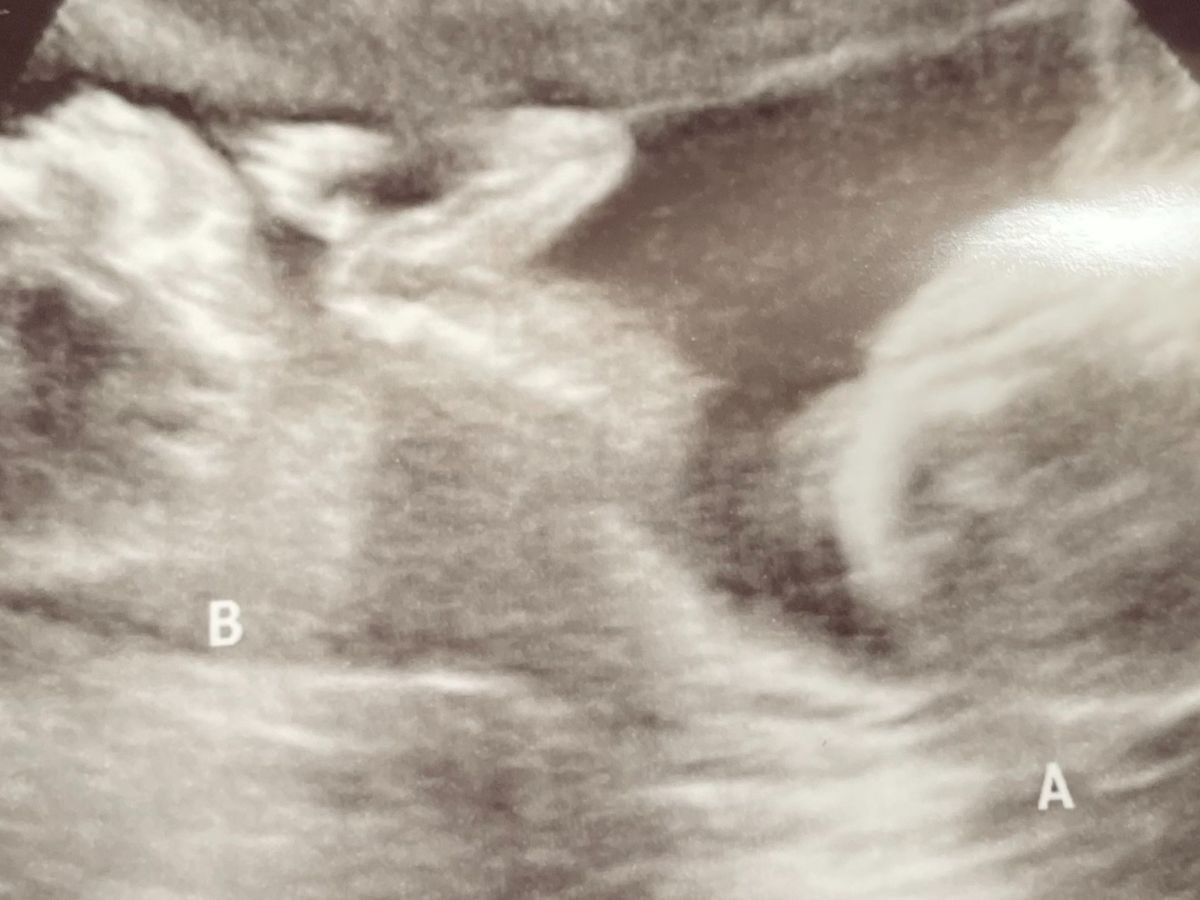

Up until a week ago, we thought we were having one baby girl. To our surprise, we found out we were having identical twins at our 20 week ultrasound. This was such exciting news!! However, nothing could have prepared us for what was to come.